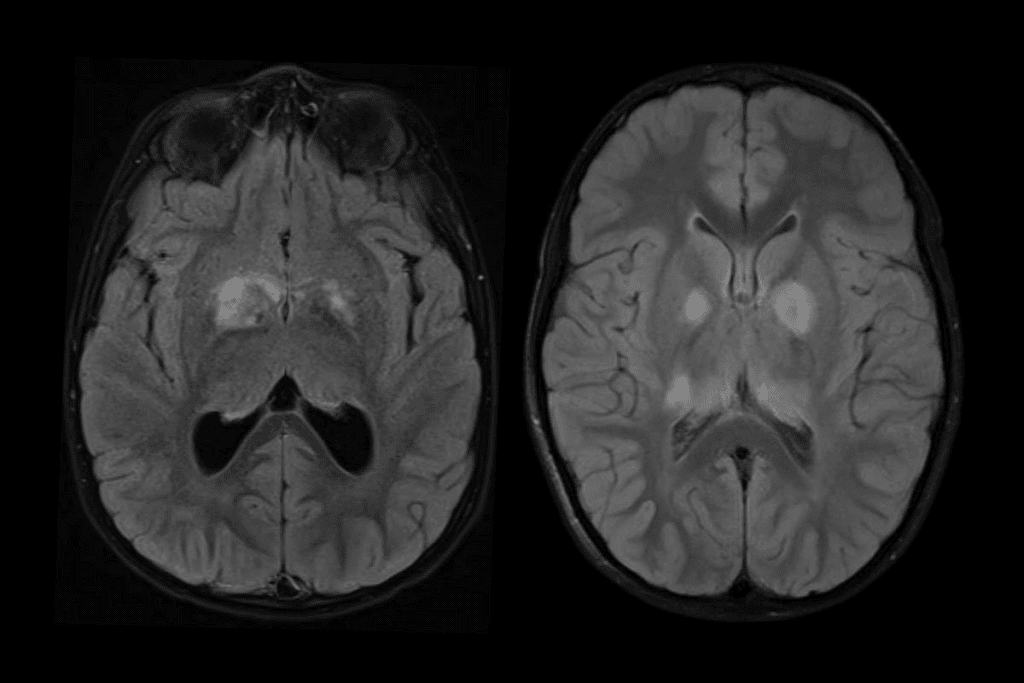

MRI and CT Scan Integration

Magnetic Resonance Imaging (MRI) and Computed Tomography (CT) scans are key tools in diagnosing brain tumors. MRI shows soft tissue details, helping find the tumor’s size and location. CT scans show the tumor’s density and if it has calcium.

Using MRI and CT scans with biopsy results makes diagnosis more accurate. For example, MRI can guide the biopsy needle to the right spot in the tumor. This increases the chance of getting a good tissue sample.